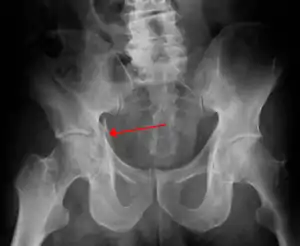

| Acetabular fracture as seen on plain X-ray |

| Posterior column | As with posterior wall injury, this also typically occurs due to dash board injury. | Posterior column + Posterior wall | These fractures are extension of elementary fractures. With involvement of posterior wall, the difficulty in treatment increases. These fractures are rarely amenable to non-surgical treatment. Due to posterior wall fracture, the hip is usually dislocated posteriorly, requiring immediate reduction of dislocation and surgical reconstruction after few days.

Posterior column with posterior wall fracture occurs due to dash board injury. Antero posterior view may give clue to these injuries, Judet views and CT scan help in knowing the extent of injury. |